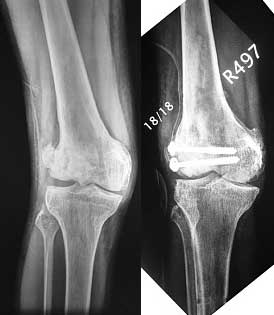

Re: Interesting case - what would you do? Knee val

Mangal Parihar 30 Апрель 2007, 17:18

I opened it up from the lateral aspect.

Freed up the non-union site with minimal disturbance to the posterior and lateral soft tissue attachments on the lateral condyle fragment.

Applied a distractor between femoral shaft and tibia, to create a space on the lateral aspect.

This brought the lateral condylar fragment into a position that seemed to be reasonably well aligned, but showed up a bone gap.

This was fixed temporarily, bone grafted with tricortical struts, and fixed by two cancellous screws. The fragment was not large enough to afford any fixation to a plate or such implant, and the screws held it compressed well to the rest of the distal femur.

Post-op - limb is well aligned, rom 0-30, but I am not pushing that right now, for the next two or three weeks.

Further plan - hope that the screws hold the fragment appropriately till union, but if the stability on table is anything to judge by, that should not be a problem.

Quadricepsplasty after a year or so, to restore flexion.

Pictures attached.

Mangal Parihar